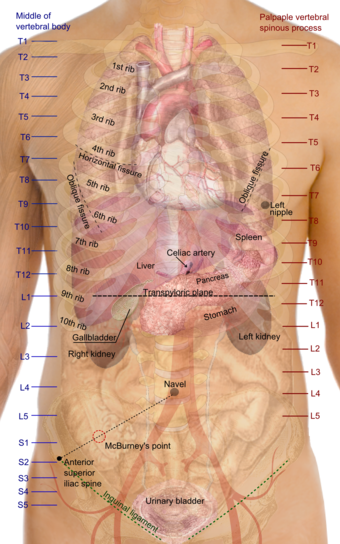

![]() اسقاطات على السطح لأجهزة الجذع، وتبدو فيه منطقة الصدر ممطوطة لأسفل حتى تقريباً نهاية oblique lung fissure خلفياً، ولكن أكثر عمقاً في حدها الأسفل الذي يناظر الحد العلوي للكبد. | |